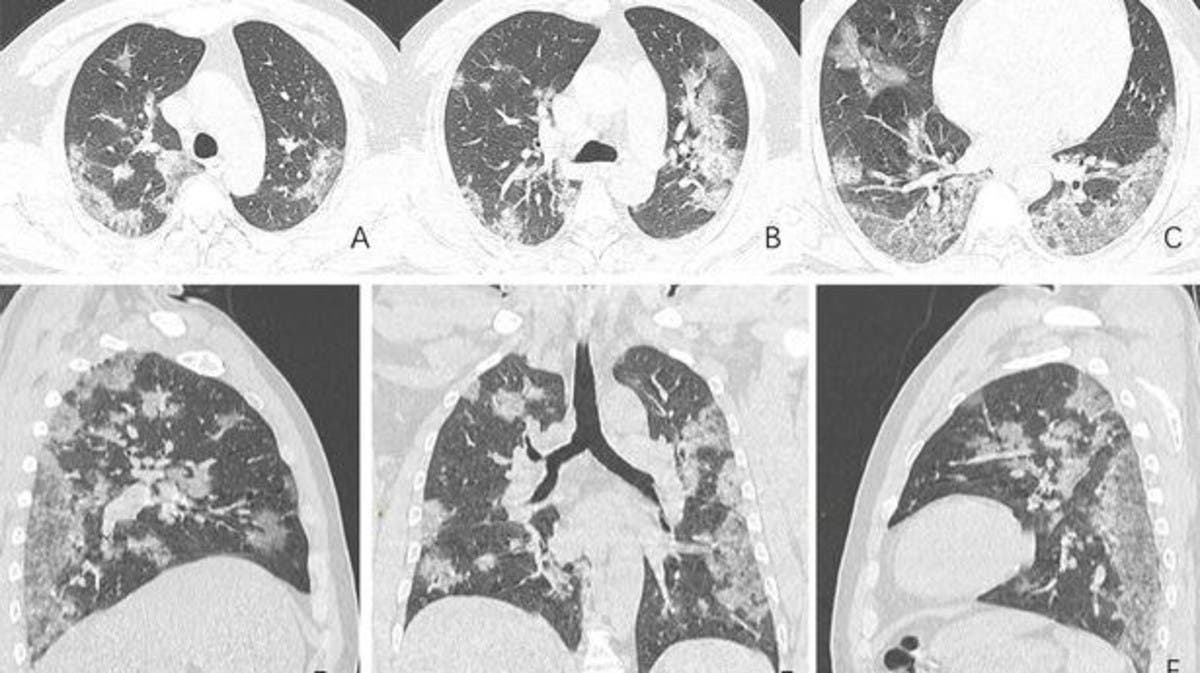

الأشعة السينية تكشف حجم الأضرار التي يسببها فيروس كورونا في الرئة صور اليوم السابع

بالصور هكذا يبدو فيروس كورونا في رئتي المصاب الحرة

هل تصلح الأشعة المقطعية لتشخيص الإصابة بفيروس كورونا

صور أشعة تكشف ما يفعله كورونا الجديد برئة ضحاياه

صور أشعة مقطعية تكشف كيف يدمر كورونا رئتي الضحايا